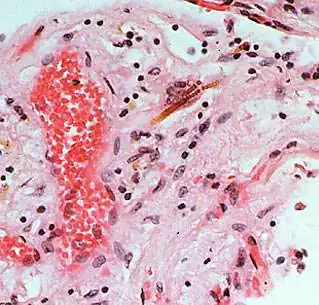

Asbestosis

Respirar bajos niveles de fibras de asbesto por largo tiempo o tener exposición corta a altos niveles de asbesto, pueden producir lesiones que parecen cicatrices en el pulmón y en la pleura. Esta enfermedad se llama asbestosis; fue la primera enfermedad pulmonar que se relacionó con el amianto y puede producir incapacidad y muerte.[23][24]

Se define como una fibrosis intersticial difusa de los pulmones, derivada de la exposición al polvo de amianto y, por lo tanto, se presenta comúnmente en trabajadores expuestos al asbesto. Las personas con asbestosis, debido a esas cicatrices en el pulmón, tienen dificultad para respirar, a menudo tiene tos, y en los casos graves sufren dilatación del corazón.

Respirar niveles de asbesto más bajos puede producir alteraciones en la pleura, generando las llamadas «placas». Las placas pleurales pueden manifestarse en trabajadores y ocasionalmente en gente que vive en áreas con altos niveles ambientales de asbesto. Los efectos de las placas pleurales sobre la respiración generalmente no son serios, pero la exposición a niveles más altos puede producir un engrosamiento de la pleura que puede restringir la respiración.